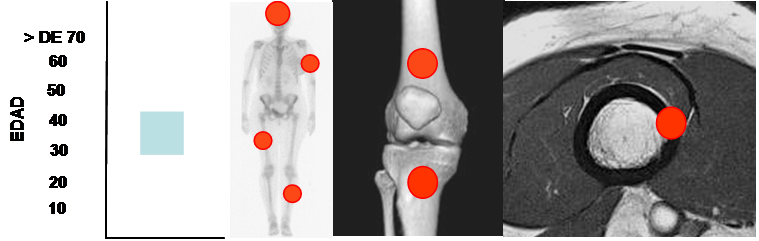

Fig 54. Osteoma.

Mayor frecuencia entre la 4º y 5º décadas. Predominio en cráneo, cara y huesos largos.

Lesión metafisodiafisiaria, de ubicación cortical.